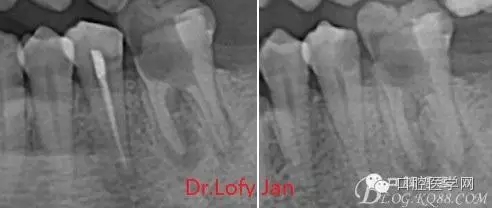

X線技術(shù)在根管治療中的重要性主要體現(xiàn)在以下幾個(gè)方面:

①有助于發(fā)現(xiàn)牙體和根尖周組織的異常改變,如牙折、牙內(nèi)吸收、髓腔鈣化及根尖囊腫;

②有助于確定牙根和根管的數(shù)目、位置、形態(tài)、方向和彎曲情況;

③有助于了解以前曾作過的治療情況,為再治療提供依據(jù);

④在操作前估計(jì)根管的工作長度;

⑤評價(jià)根管充填的質(zhì)量以及療效。